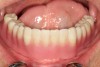

Fig 10. The prosthesis was placed onto the edentulous ridge and complete adaptation to the tissues and implants was confirmed. The patient was very pleased with the final result.

Figure 10